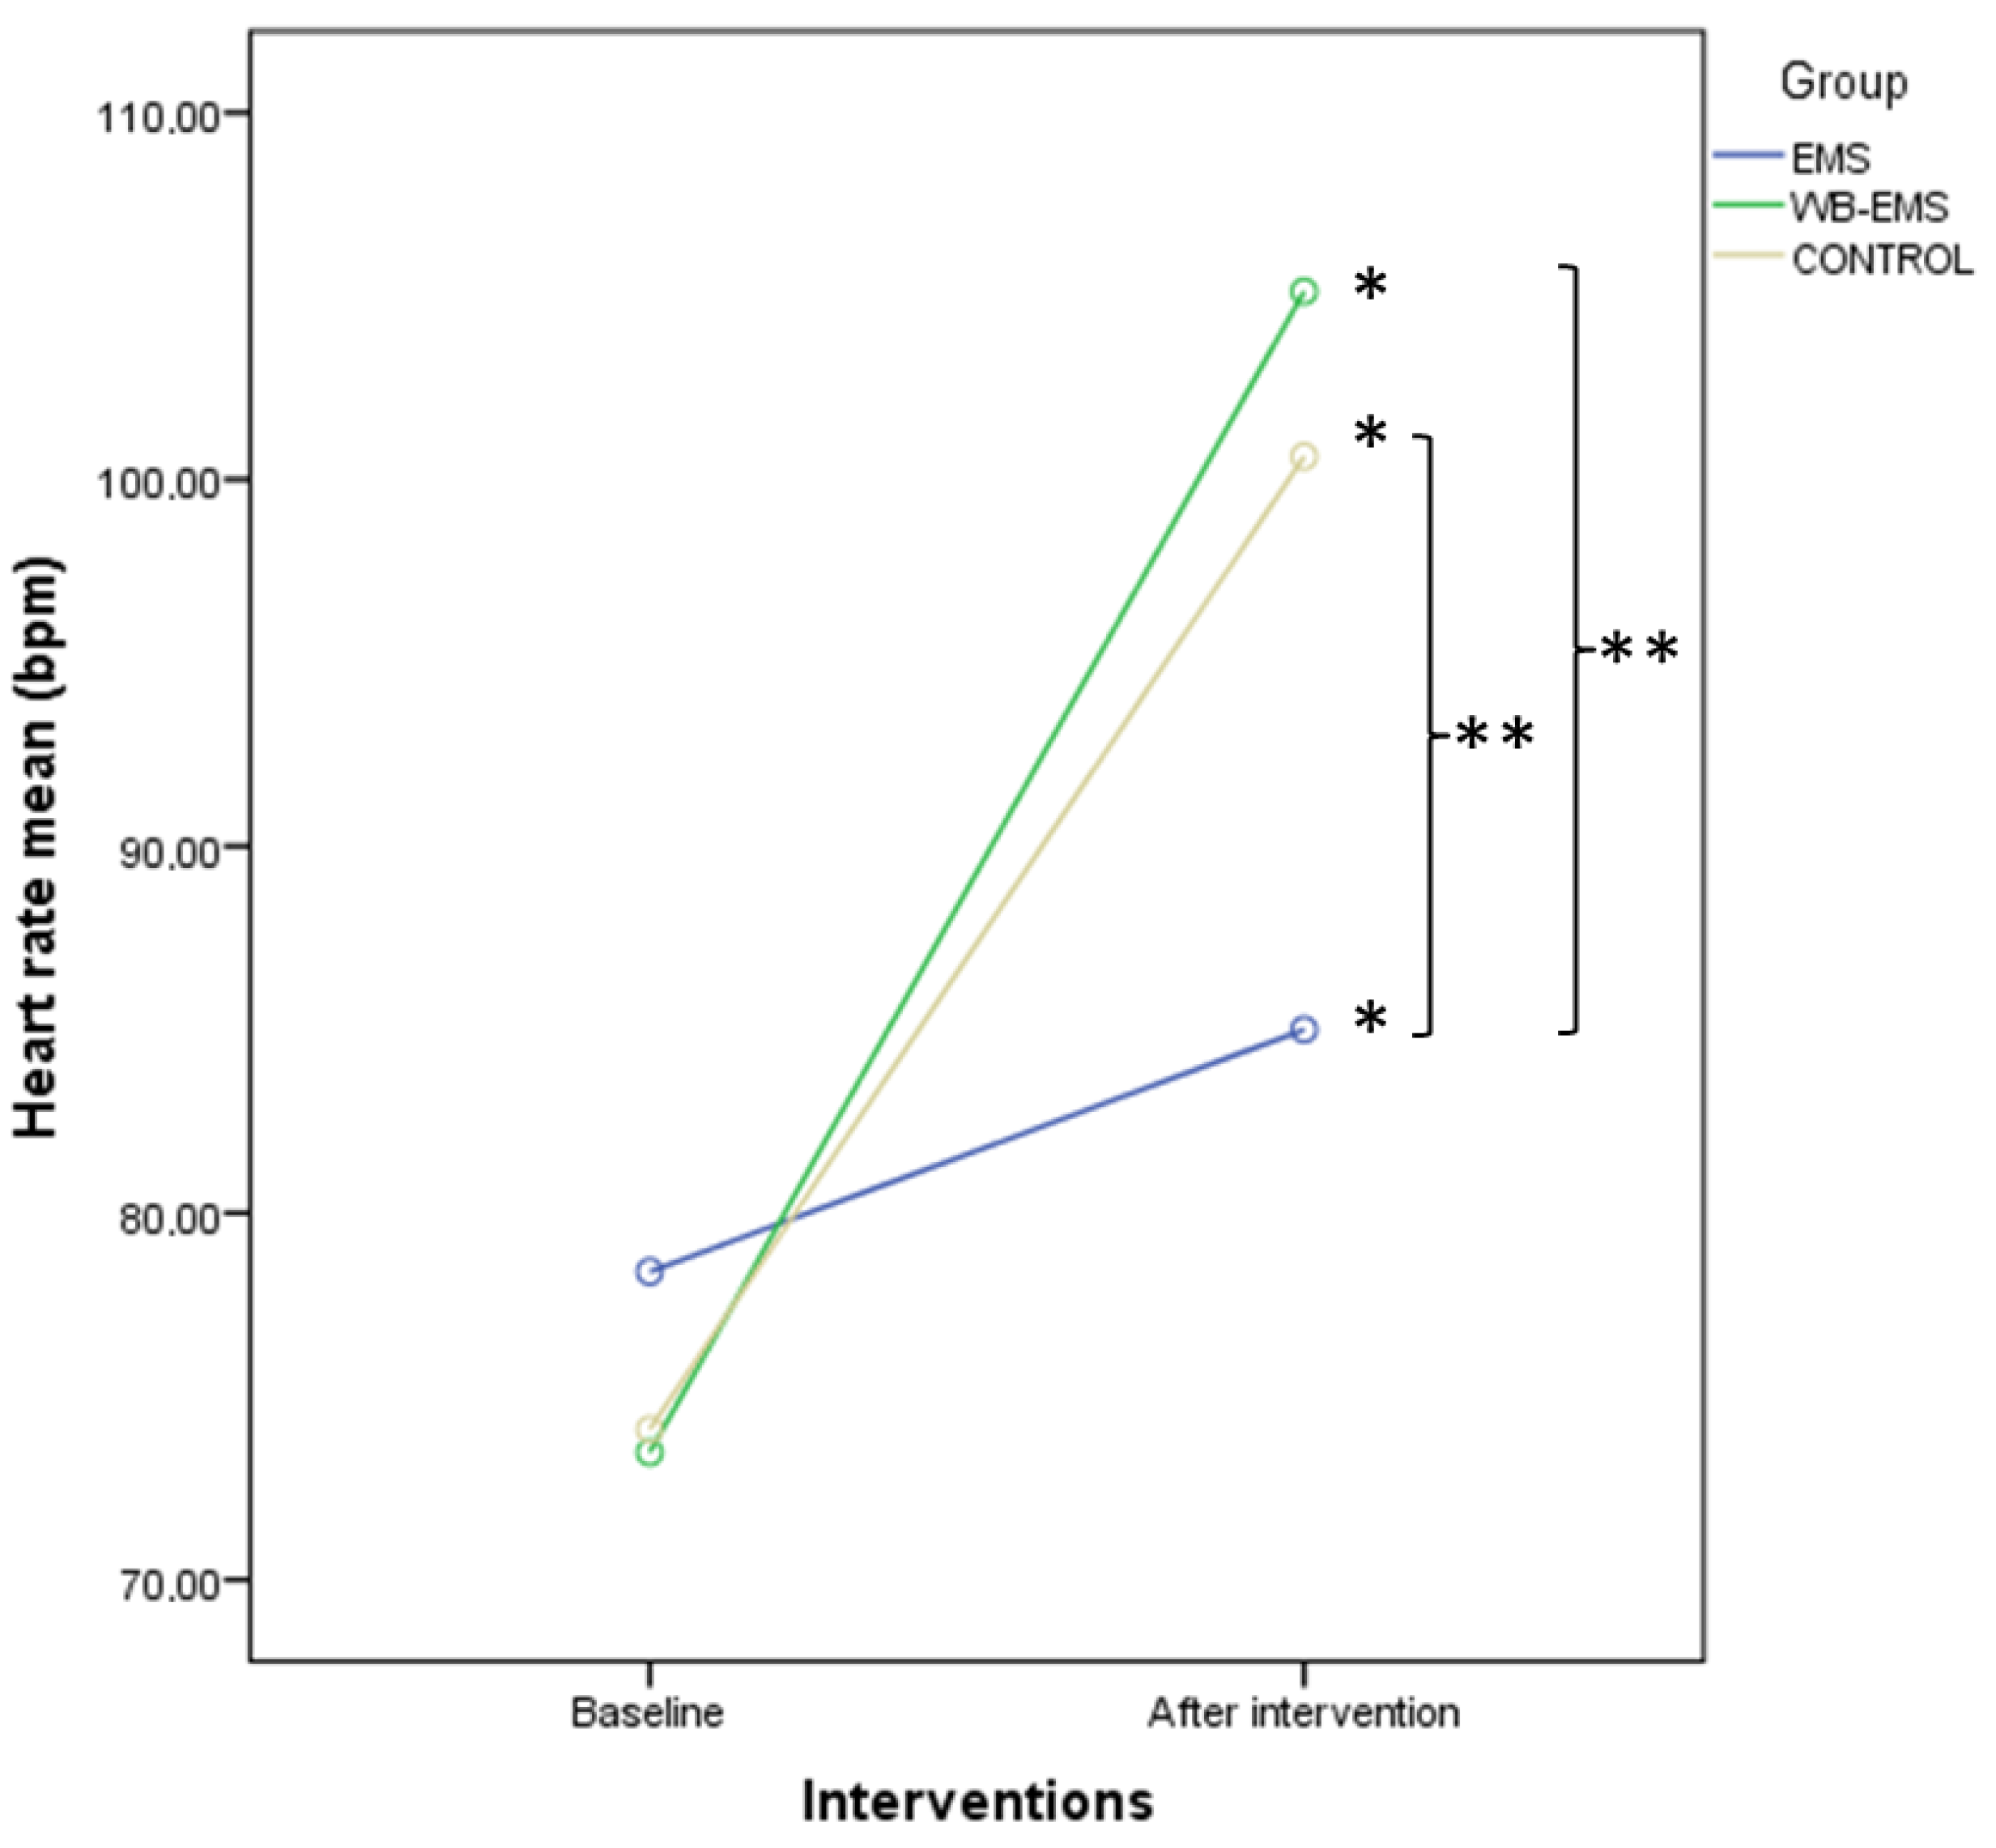

3.3. Outcome Measurements Differences after Interventions

3.4. Two-Way ANOVA of Repeated Measurements for Intra- and Intergroup Comparisons

| HR (bpm) | 78.40 ± 15.49 (51–118) | 85.00 ± 22.28 (53–137) | 6.60 ± 12.42 (−22–31) | 73.47 ± 13.16 (51–100) | 105.12 ± 18.12 (59–137) | 31.65 ± 16.22 (1–71) | 74.10 ± 15.68 (54–116) | 100.62 ± 20.81 (59–137) | 26.52 ± 16.22 (−4–75) | <0.001 * |